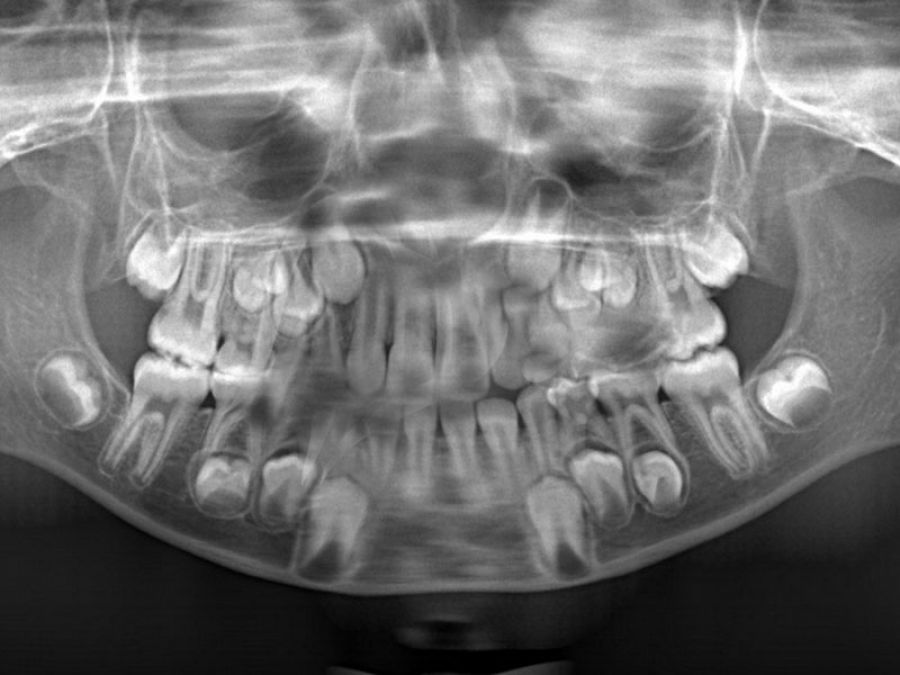

Yirmi yaş dişleri olarakta bilinen üçüncü azı dişleri sıklıkla kemik içerisinde gömülü kalabilir ya da yanlış bir pozisyonda sürebilir. Bu durumda cerrahi yöntemlerle lokal anestezi altında çekilmeleri gerekmektedir. Bazen gömülü kalmış köpek dişlerine de aynı tip cerrahi işlemler uygulanabilir.